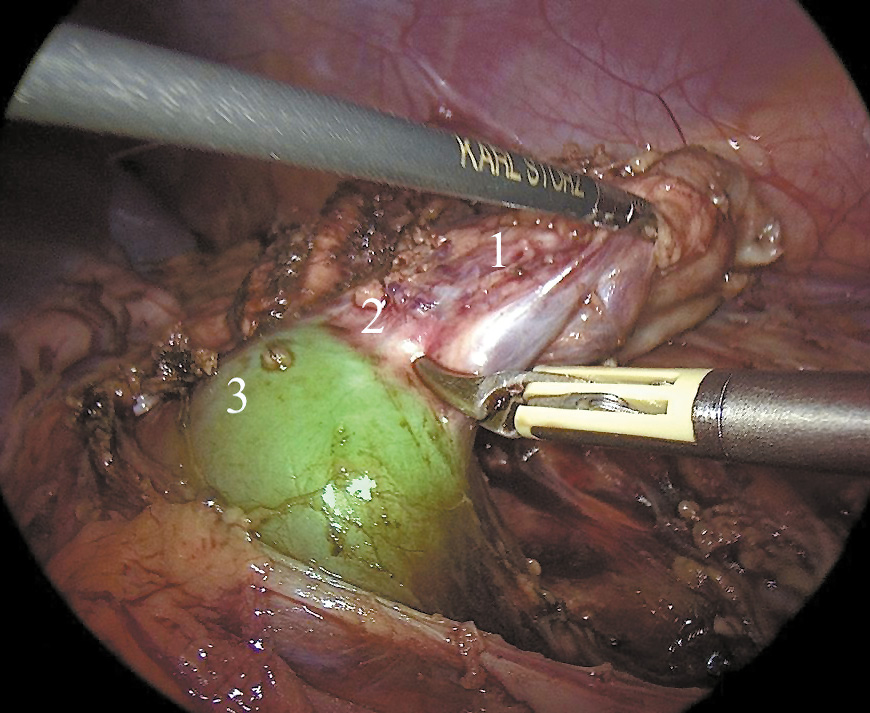

После обнажения передней стенки левой половины ПОП мы осмотрели ткань почки и почечные сосуды, питающие левую половину ПОП (рис. 2). Деликатными действиями мобилизовали сосуды и освободили левую половину ПОП от перивисцеральных сращений до уровня перешейка, соединяющего её с правой половиной ПОП.

Рис. 2. Визуализация подковообразной почки в режиме наложения флуоресцентного изображения: 1 — левая половина подковообразной почки, 2 — перешеек подковообразной почки, 3 — правая половина подковообразной почки.

Затем внутривенно болюсно ввели ICG в дозе 0,25 мг/кг. Режим флюоресценции ICG-NIRF активировали нажатием кнопки на головке камеры, благодаря чему флюоресцентная визуализация была доступна в режиме реального времени, позволяя идентифицировать почечные сосуды, паренхиму почки и верхние мочевые пути — лоханку почки и верхнюю треть мочеточника. Компоненты RUBINA™ предлагают различные режимы визуализации сигнала ICG-NIRF. В зависимости от предпочтений хирурга и области применения ICG-NIRF данные могут отображаться в различных режимах: режим наложения, монохромный режим, режим цветного картирования.

В режиме наложения данные ICG-NIRF накладываются на стандартное изображение в обычном светодиодном свете. При использовании этого режима здоровая правая половина ПОП окрашивается насыщенным зелёным цветом, поражённый левый сегмент не даёт признаков свечения (см. рис. 2).

Монохромный режим может отображать сигнал ICG-NIRF в монохромном белом цвете на черном фоне для лучшей дифференциации флюоресцирующих тканей — правая половина ПОП окрасилась насыщенным белым цветом, поражённый левый сегмент не окрасился (рис. 3).

Рис. 3. Визуализация подковообразной почки в режиме монохромного изображения: 1 — левая половина подковообразной почки, 2 — перешеек подковообразной почки, 3 — правая половина подковообразной почки.

Использование ICG-визуализации было очень полезным для идентификации здоровой ткани, которая окрасилась в насыщенный зелёный цвет через 2 мин после внутривенного введения ICG. Этот тест подтвердил границы функционирующей почечной паренхимы и помог выбрать границы резекции почки.

Затем мы пересекли перешеек почки на границе свечения, используя технологию электролигирования BiClamp компании ERBE (рис. 5). Мочеточник удалённой части выделяли как можно дистальнее и герметизировали на уровне мочевого пузыря, используя клипсы Hem-o-Lok.

Рис. 5. Лапароскопическая резекция левой половины подковообразной почки, визуализация в режиме наложения изображения: 1 — левая половина подковообразной почки, 2 — перешеек подковообразной почки, 3 — правая половина подковообразной почки.